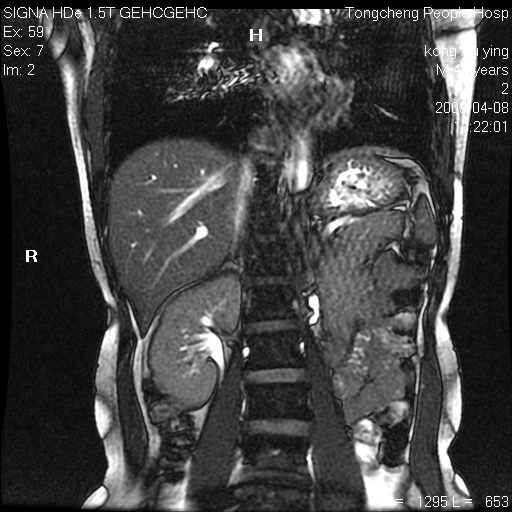

标题: CL1008:【经典】胆囊石榴籽样结石。

女,41岁。健康体检——彩超提示:胆囊显示不清。平素健康,无不适感。

腹部mr扫描及mrcp,图像如下: